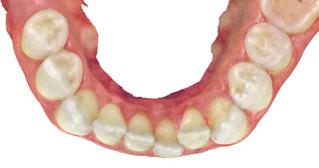

Figure 2: Initial lower occlusal

Figure 1: Initial center photo

This case involves a 13-year-old female patient with a complex malocclusion that includes multiple dental and skeletal issues. During the initial consultation, clinical evaluation showed severe maxillary crowding along with generalized spacing in the mandibular arch. The patient’s occlusal relationships were asymmetric, with a Class I molar relationship on the right side and a Class II molar relationship on the left. Notably, an anterior crossbite was observed, further complicated by a narrow, V-shaped maxillary arch — a common presentation that often exacerbates anterior-posterior discrepancies and limits functional occlusion. The patient also demonstrated poor oral hygiene, which is a key indicator of an indirect bonding system that does not reduce excess flash. ODB is superior in flash reduction, by being able to remove excess adhesive from three sides of the bracket instead of competitors who only remove adhesive from one side of the bracket. The presence of adhesive around brackets contributes to surface roughness which leads to plaque accumulation.1 Flash reduction will be very important for every patient’s orthodontic success (Figures 1-3).